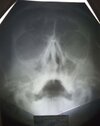

Всем привет. Ну чо, сходил в больницу - сдался, двусторонний синусит, отеки, хуëки, слизистой, гноя нет, потому что вовремя начал пить антибиотики, и да, я бля красавчик, среагировал оч вовремя)))

Снимочек моего довольного эбальца)))